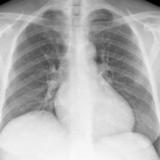

Bivent failure

Date: 11/05/2005

Views: 2659